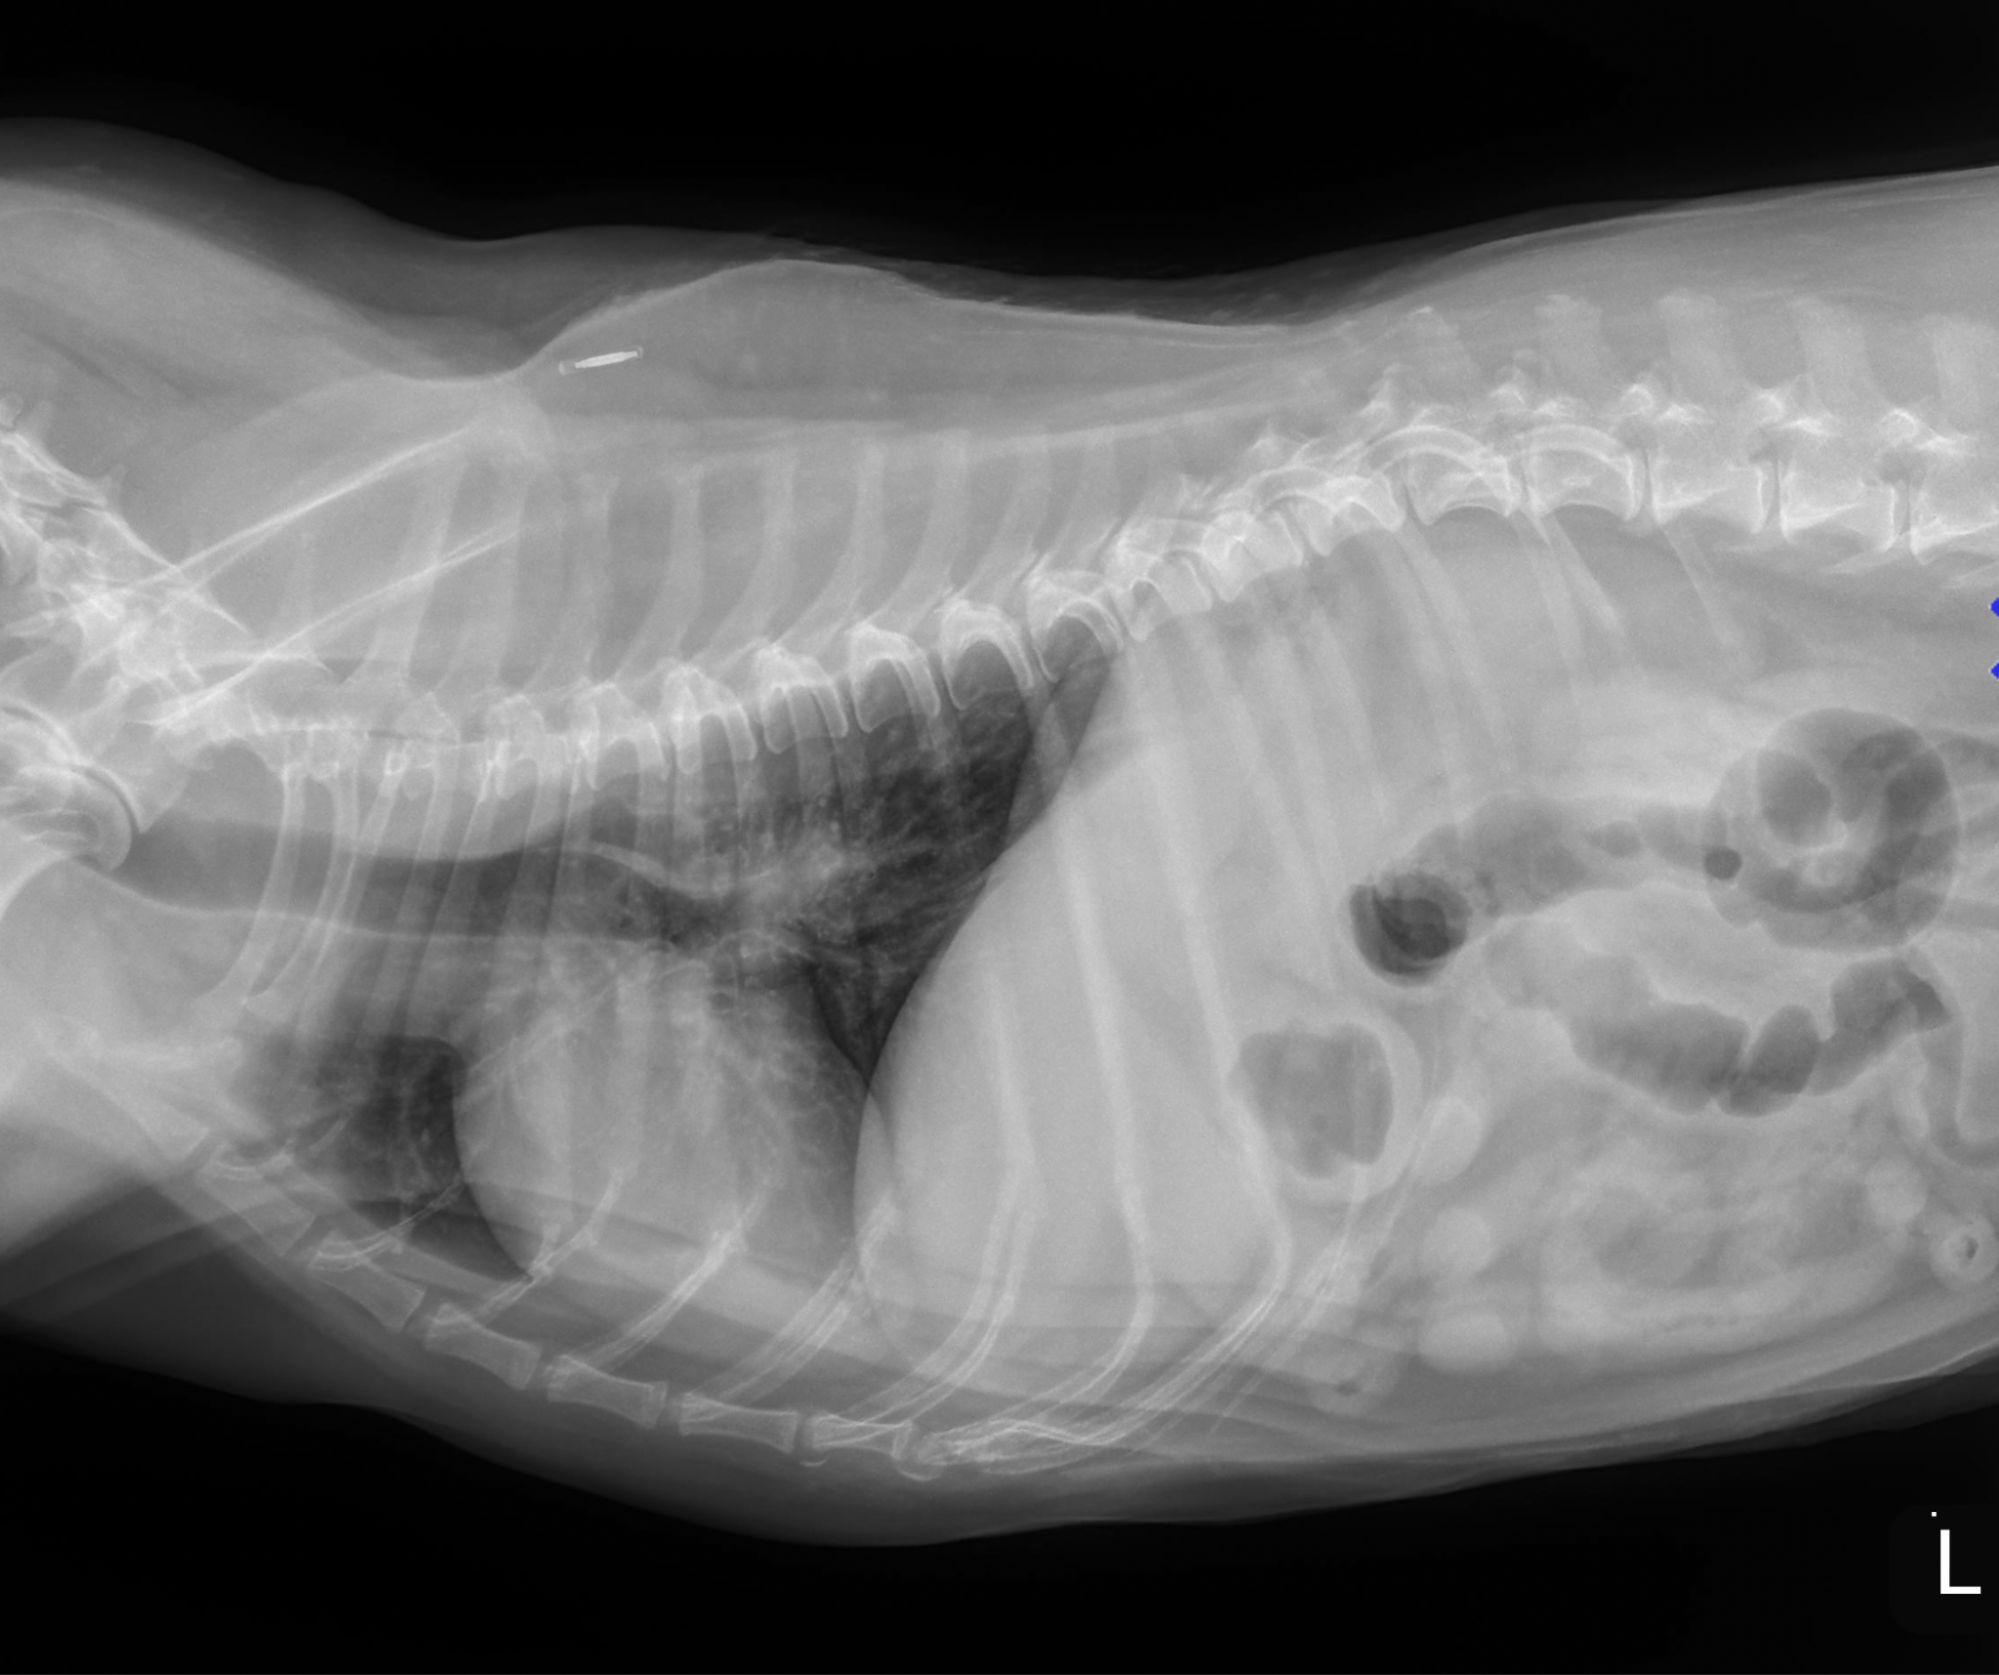

The following morning, thoracic radiographs were submitted for review by Dr. Mark B. Taylor, DVM, DACVR.

Findings included:

• Mild left-atrial enlargement

• Early interstitial perihilar pulmonary markings

• Hepatomegaly

• Suspected cystic calculi

An echocardiogram was recommended, and judicious fluid therapy with a possible furosemide (Lasix) trial was discussed. Based on these findings and the case progression, a critical care consultation was advised.